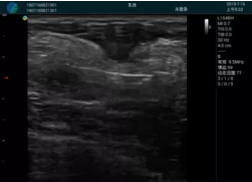

可視化穿刺引導

M20實時引導:向包塊后方間隙注射利多卡因

清晰顯示腺體內低回聲快影,邊界清晰,包膜較光滑

確定進針路徑并實時監(jiān)測抽吸針與腫塊位置關系

抽吸針進入腫塊內部進行旋切

抽吸過程中可見腫塊明顯縮小,并根據腫塊位置改變針道位置

抽吸旋切后再進行超聲復查,原腫塊區(qū)域未見殘留組織及出血

超聲引導下抽吸旋切取出的腫塊組織